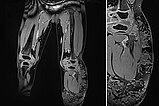

Die koronare Magnetresonanztomographie in T2-Wichtung, fettgesättigt, zeigt die stark hyperintense (fast weiße), zum Teil zystische Läsion am linken Bein im subkutanen Fettgewebe.

In der Magnetresonanztomographie in T1-Wichtung, fettgesättigt, nach Kontrastmittelgabe zeigt die Läsion am linken Bein im subkutanen Fettgewebe keine zentrale Kontrastmittelanreicherung. Allenfalls die Zystenwände reichern zart Kontrastmittel an (Ausschnittvergrößerung rechts). Somit im MRT das Bild einer lymphatischen Malformation.